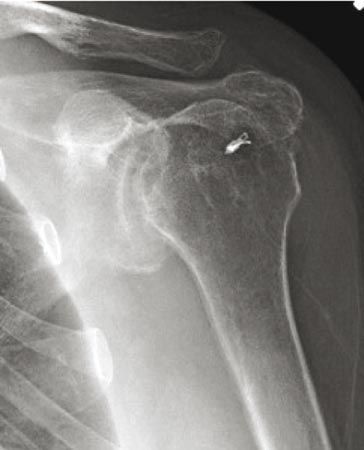

Technique Ostéotomie de centrage de la tête humérale pour le traitement des séquelles de la paralysie obstétricale de l'épaule , Arnaldo Amado Ferreira Neto University of São Paulo, Department of Orthopaedics and Traumatology, São Paulo, Brazil N°211 - Février 2012 ● 9 min de lecture